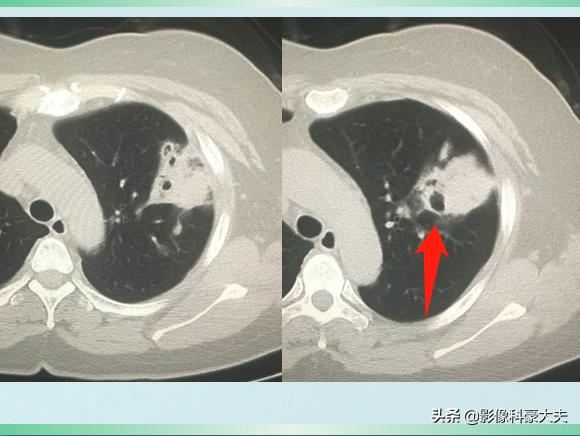

我们先不公布答案,继续看她治疗10天后的复查CT:

对比前两次片子,黑色空洞影变得更大了,周围的白色炎症斑片影吸收好转了。